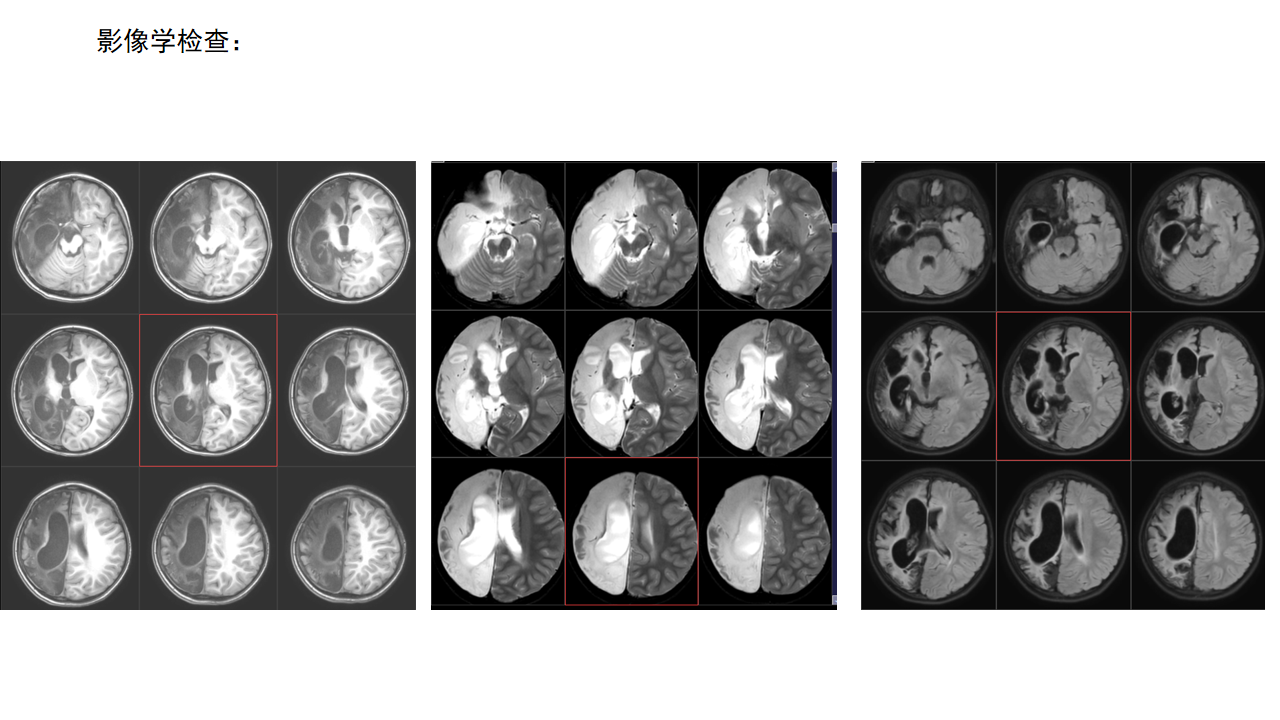

右侧功能性大脑半球切除术

杨文桢

兰州大学第二医院